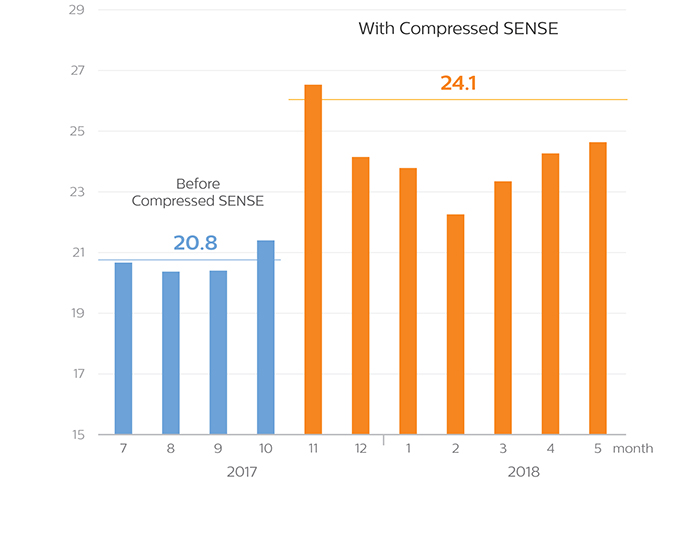

KOYASU Neurosurgical Clinic sees an average of 14% higher patient throughput after implementing Compressed SENSE for fast MRI

In the months after they integrated Compressed SENSE in their MRI ExamCards, KOYASU Neurosurgical Clinic (KNC) in Kanagawa, Japan, has been able to scan over three additional MRI patients per day on average. Compressed SENSE made it possible to decrease time slot length from 20 to 15 minutes per patient without sacrificing image quality. This resulted in several observable benefits for the KNC team.

KNC decided to add the Compressed SENSE functionality on their Ingenia 3.0T CX. On average, about 27 patients per day were scanned on this MRI scanner prior to implementation of Compressed SENSE. Brain examinations were by far the largest fraction of examinations, though lumbar spine, cervical spine and a few other exams were also done.

“In September and October our average number of patients per day was about 27 on Ingenia 3.0T CX. We started using Compressed SENSE in November and we completed that month with scanning an average of more than 33 patients per day. That is 6 more patients per day than in September and October!”

A higher average number of patients scanned per day

in each month after KNC started using Compressed SENSE

Average number of examinations per day

This 11-month diagram shows that the average number of patient examinations per day on the Ingenia 3.0T CX has increased since Compressed SENSE is used. Although the highest throughput was achieved in the first month of using Compressed SENSE, the graphs demonstrate the realization of higher throughput of 14% on average over a longer term.

Average number of examinations per day (9:00 - 18:00)

In order to exclude the effect of overtime, the daily average number of patients scanned between 9:00 and 18:00 h was also calculated. It confirms that on average three additional patients per day were scanned since implementation of Compressed SENSE.